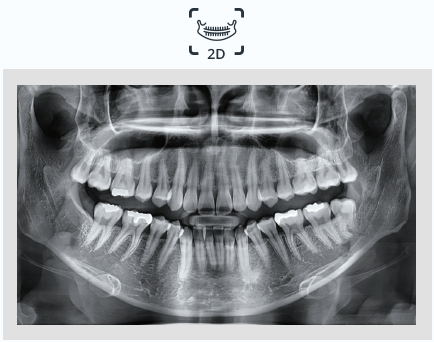

맨 처음 치과에 방문했을 때 파노라마 엑스레이 촬영해보신 경험 다들 있으실겁니다.

큰 기계 앞에 서서 앞니로 플라스틱 부분을 물고 있으면 기계가 돌아가면서 촬영하게 되는데요.

이 때 촬영하는 파노라마는 2D로, 잇몸뼈와 신경, 치아 뿌리부분까지 평면으로 보여줍니다.

파노라마사진 예시

출처) 바텍 아메리카 홈페이지